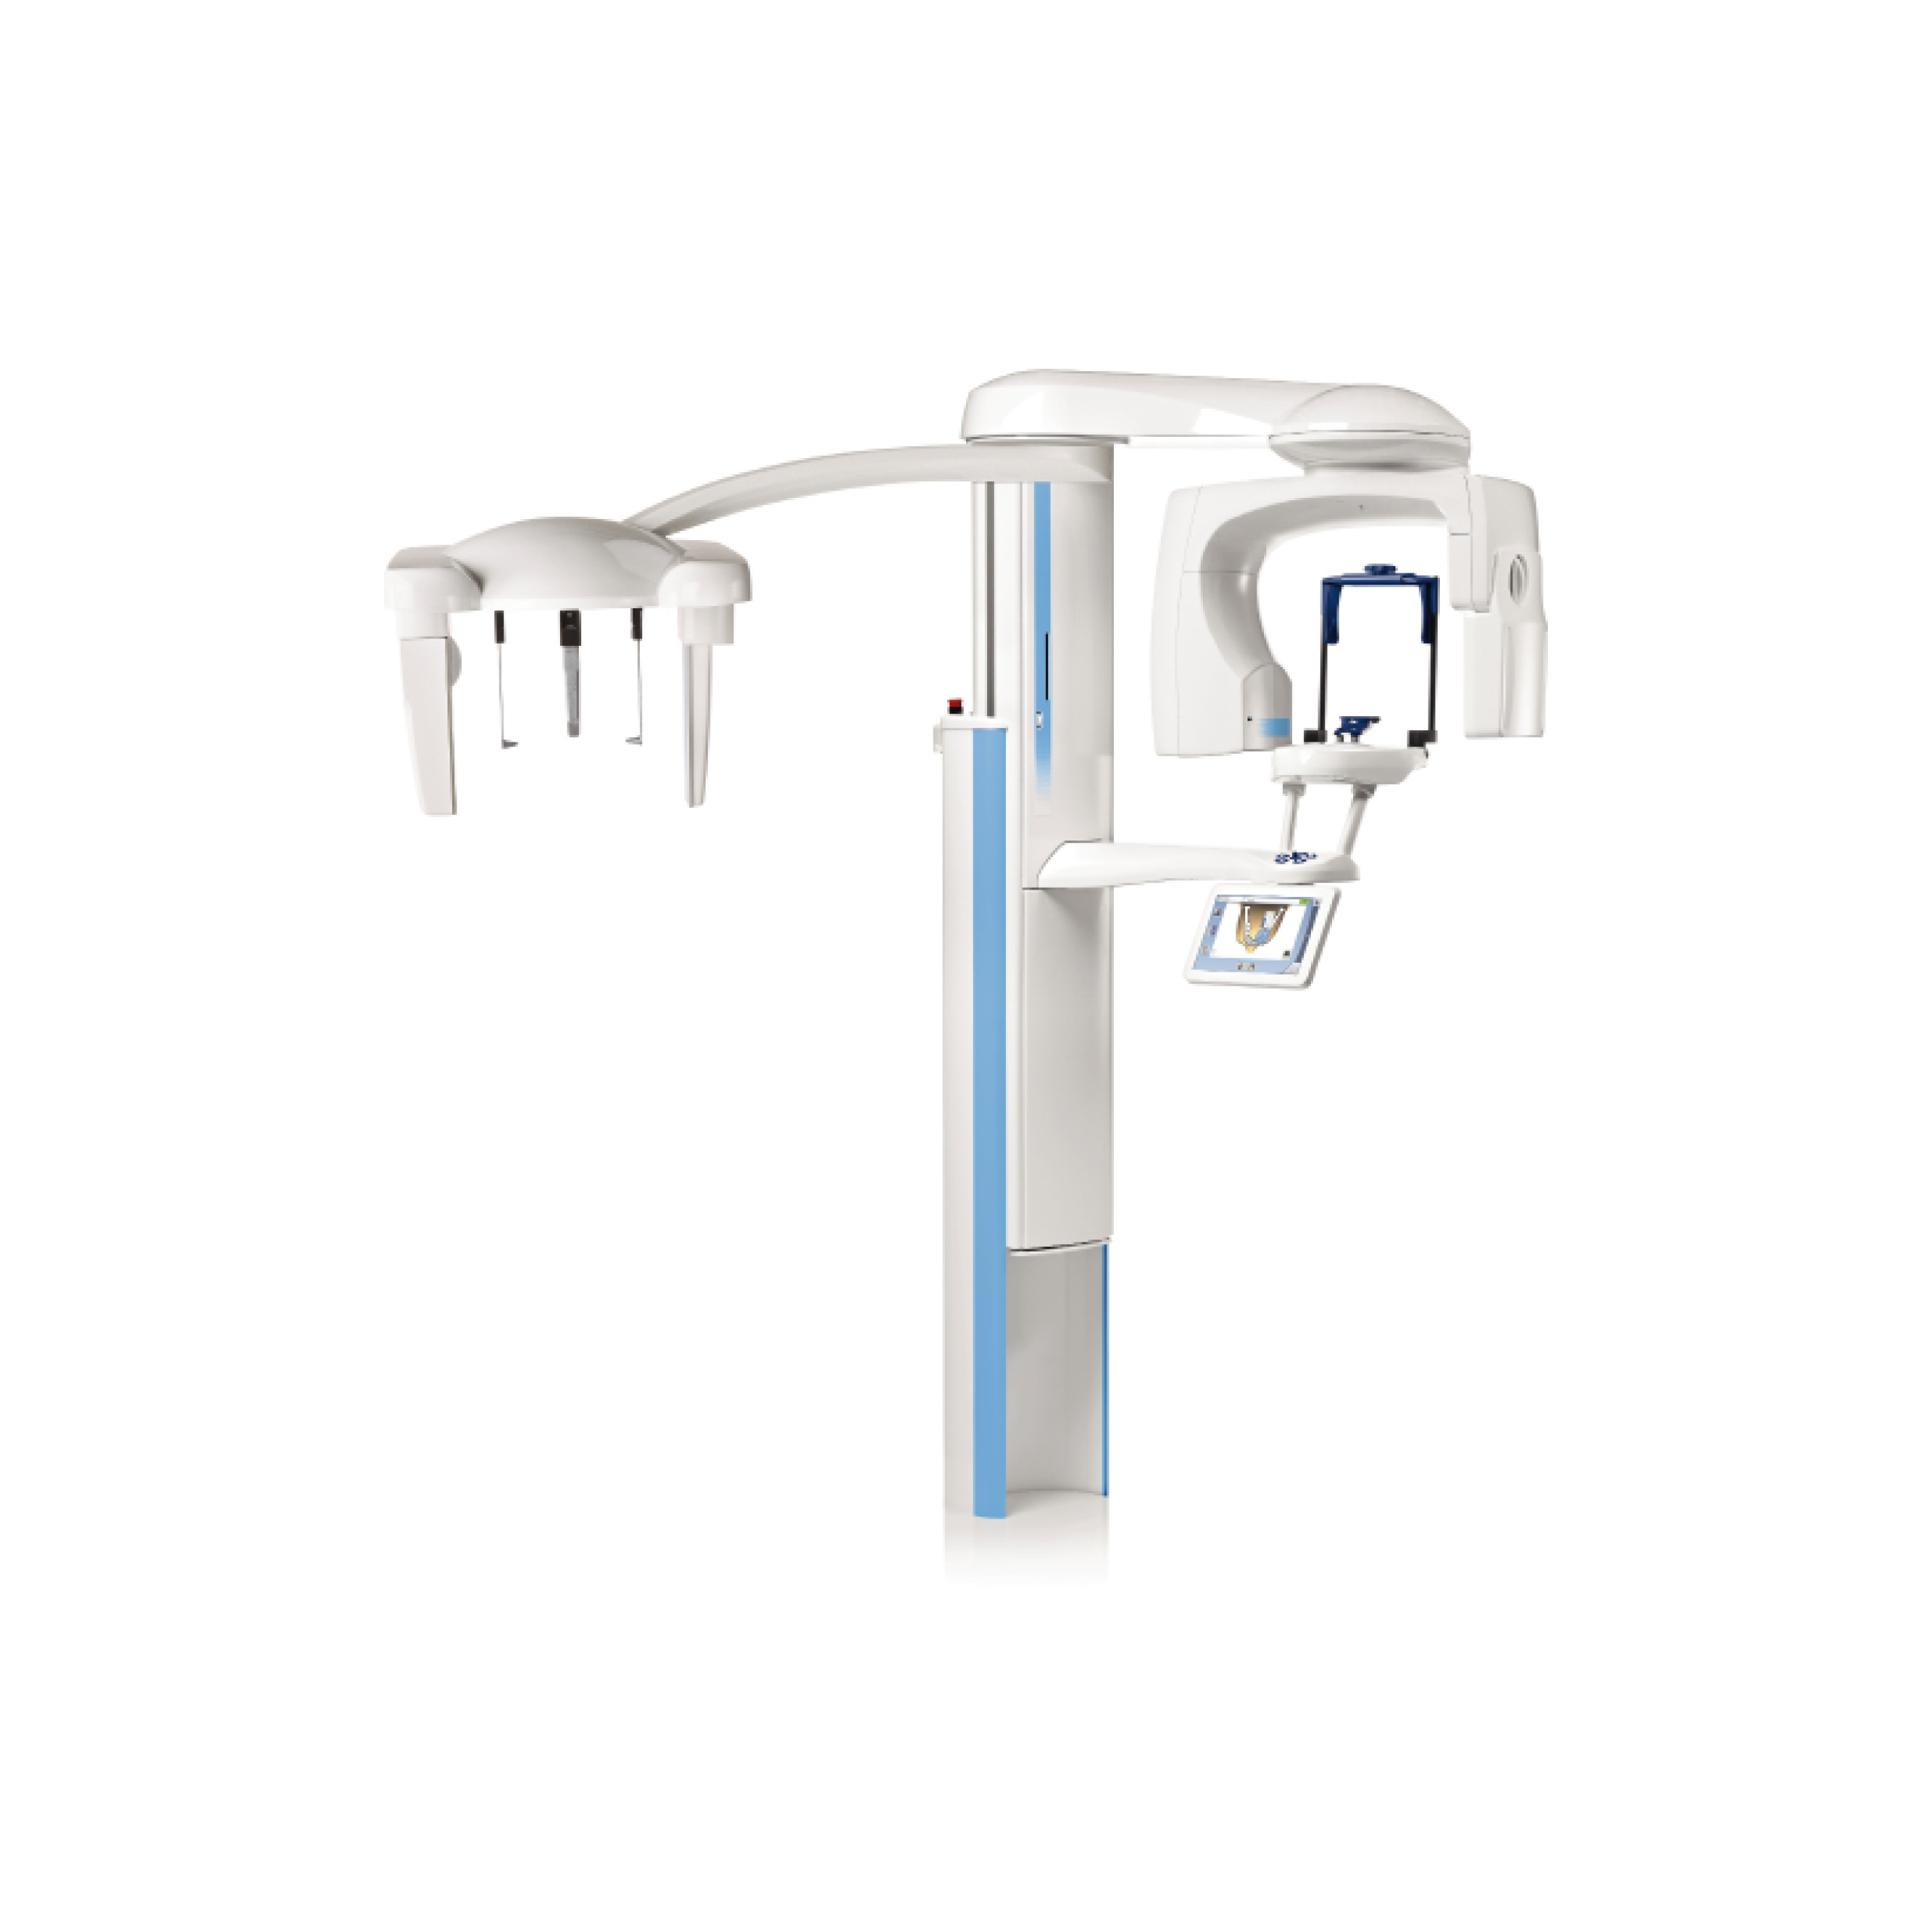

Planmeca ProMax 3D Classic

Provides a clear view of the mandible and maxilla, as the units imaging sensor covers the entire dentition.

Planmeca ProMax 3D Plus

A great choice for capturing more than just the dentition, with an extended variety of volume sizes available.